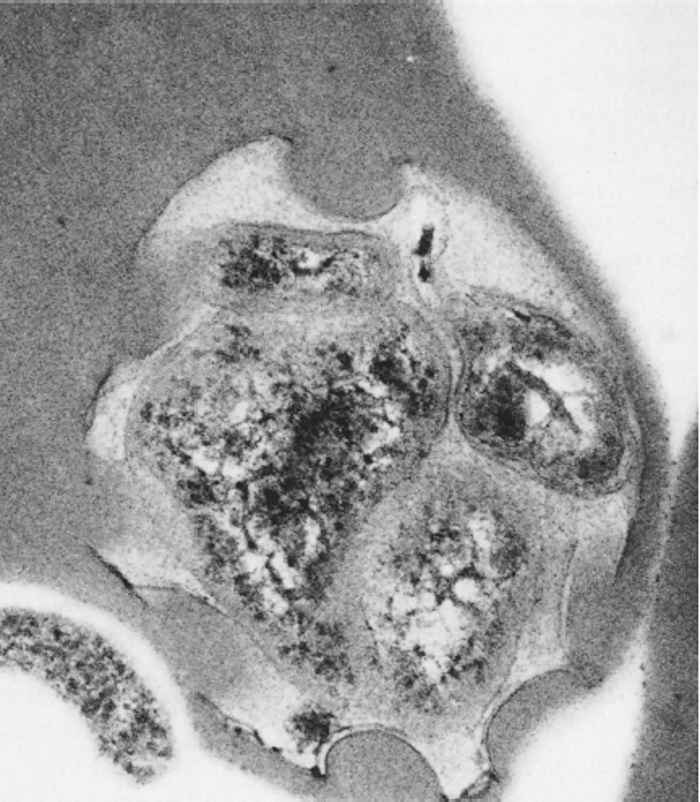

Upon tick transmission, A. marginale enters and replicates in erythrocytes, though endothelial cells may also be infected27. In Giemsa-stained blood smears, the intra-erythrocytic organisms are dense, deeply purple, roundish inclusions 0,3 to 1,0 μm in diameter (Figure 1) and (Figure 2). Anaplasma marginale and A. centrale are morphologically indistinguishable, though A. centrale is typically located in a more central position in the erythrocyte, while A. marginale tends to remain in the periphery as their names indicate. Ultrastructurally, Anaplasma inclusions are bound by a membrane and can contain up to eight bacteria. Typical of the Anaplasmataceae, the individual bacteria have outer and inner cell membranes50, 146 (Figure 3).